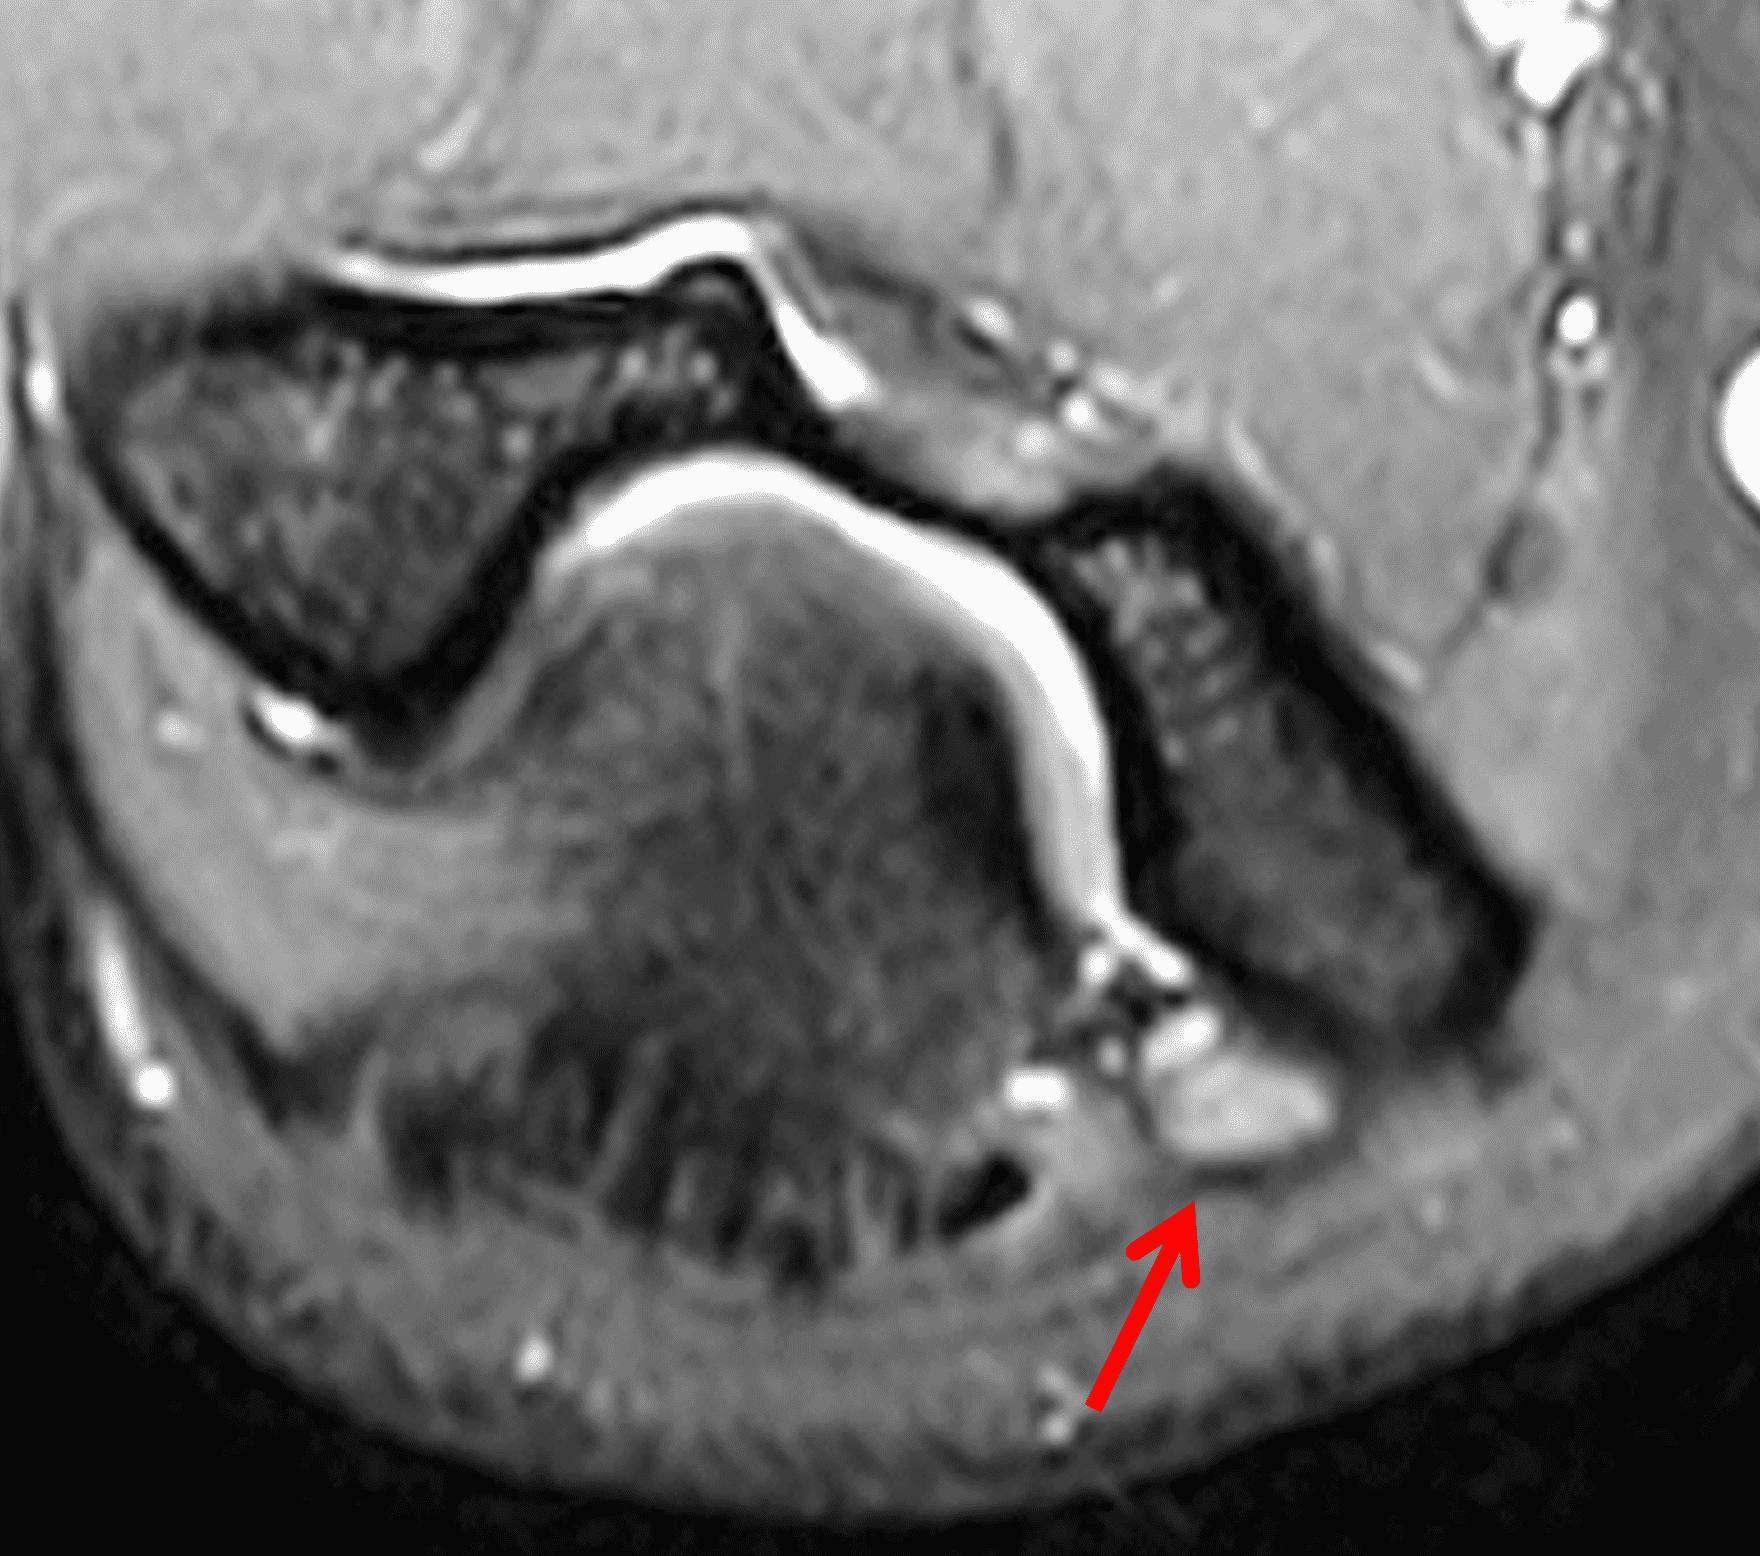

Figure 2: At the level of the cubital tunnel (2A and 2C), identifiable by the thin cubital tunnel retinaculum (yellow arrow), the ulnar nerve (red arrow) is focally enlarged and hyperintense compared to the nerve more distally (2B and 2D), where it lies between the two heads of the flexor carpi ulnaris muscle (asterisks). No soft tissue mass is present.